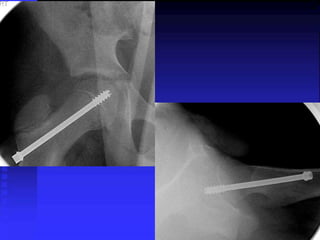

= Femoral neck displaces ant. producing an

The goal of treatment for SCFE is

Screw advancement until

FIVE

threads engage the epiphysis

The goal oftreatment for SCFE is to prevent further slippage and to stabilize the epiphysis Screw advancement until FIVE threads engage the epiphysis

• 58.